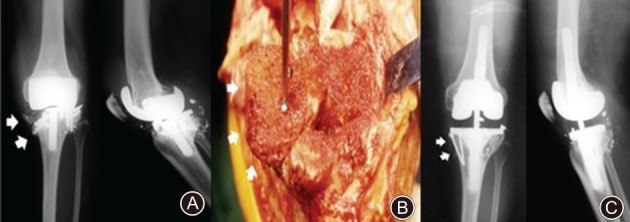

Several studies have demonstrated that the use of femoral head structural allograft might improve the clinical outcomes for patients with severe bone defects in RTKA9, 32. A prospective case series from the Royal London Hospital demonstrated that the use of femoral head structural allograft along with long stemmed components can achieve a successful result in the management of severe bone loss during RTKA33. Chun et al. assessed the mid‐term to long‐term clinical and radiographic results for severe bone defects of 27 patients undergoing RTKA using a fresh frozen femoral head allograft and a standard condylar implant with a diaphyseal‐engaging stem (Fig. 7)53. In their study, 26 out of 27 knees were observed to have no collapse, disease transmission or stress fractures, and the mean range of motion had increased from 71° to 113° and the mean Hospital for Special Surgery knee score had improved from 46 to 83 points, providing a reliable and durable result.

Figure 7.

(A) Anteroposterior and lateral radiographs show a severe osteolysis in proximal tibia and distal femur with metal breakage (white arrow). (B) The femoral head allograft was stabilized with screws at the proximal tibia (white arrow). (C) The allograft remained intact with minimal resorption at 6 years after surgery (white arrow).